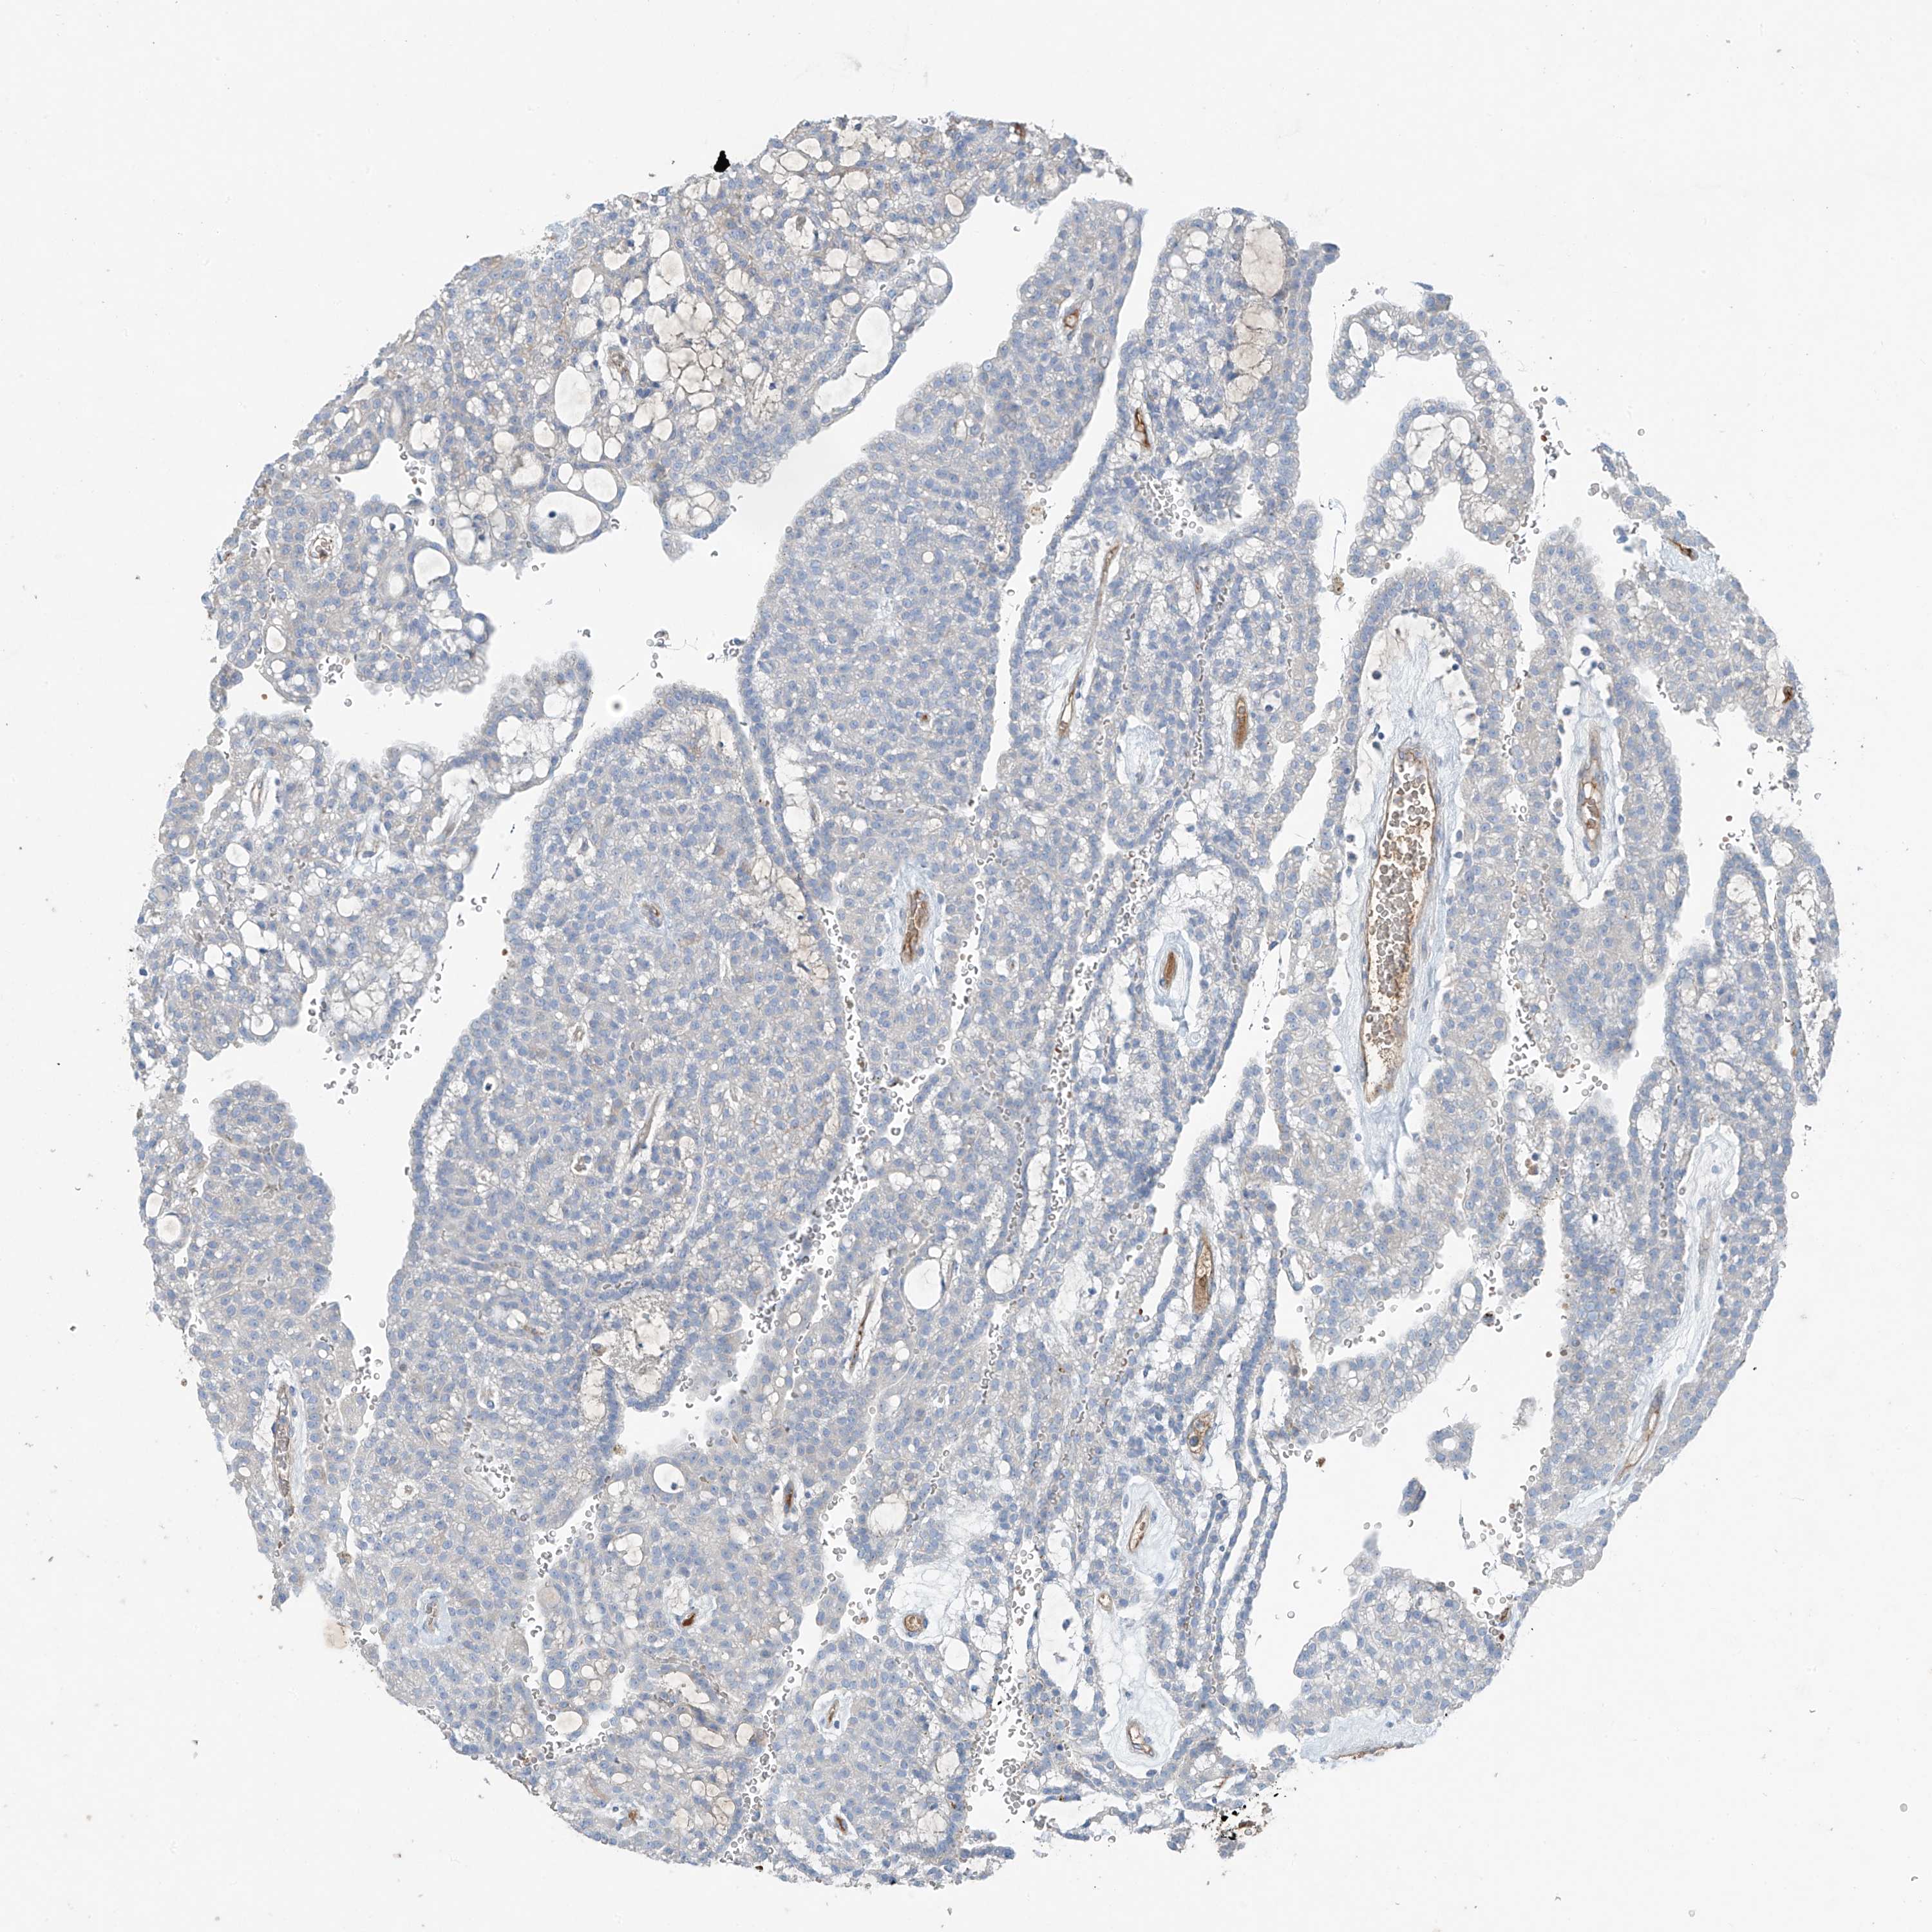

CANCER RENAL CANCER Show tissue menu

KICH TCGA KIRC TCGA KIRC VALIDATION KIRP TCGA PROTEIN RCC CPTAC PROTEIN EXPRESSION

KIDNEY CHROMOPHOBE (TCGA) - Interactive survival scatter ploti

The Survival Scatter plot shows the clinical status (i.e. dead or alive) for all individuals in the patient cohort, based on the same data that underlies the corresponding Kaplan-Meier plots. Patients that are alive at last time for follow-up are shown in blue and patients who have died during the study are shown in red.

The x-axis shows the expression levels (FPKM) of the investigated gene in the tumor tissue at the time of diagnosis. The y-axis shows the follow-up time after diagnosis (years). Both axes are complimented with kernel density curves demonstrating the data density over the axes. The top density plot shows the expression levels (FPKM) distribution among dead (red) and alive patients (blue). The right density plot shows the data density of the survived years of dead patients with high and low expression levels respectively, stratified using the cutoff indicated by the vertical dashed line through the Survival Scatter plot. This cutoff is automatically defined based on the FPKM cutoff that minimizes the p-score. The cutoff can be changed by dragging the vertical line or by entering a cutoff value in the square labeled "Current cut-off".

Under the Survival Scatter plot the p-score landscape (black curve; left axis) is shown together with dead median separation (red curve; right axis). Dead median separation is the difference in median mRNA expression between patients who have died with high and low expression, respectively. It is calculated as follows: median FPKM expression of dead patients with high expression - median FPKM expression of dead patients with low expression. This is intended to aid the user in visually exploring custom cutoffs and the associated p-scores and dead median separation.

Individual patient data is displayed and can be filtered by clicking on one or more of the category buttons on the top of the page. Categories describing expression level and patient information include: high, low, alive, dead, female, male and tumor stages. The scale of the x-axis can be toggled between linear and log-scale by clicking on the "x log" button. Mouse-over function shows TCGA ID, patient information and mRNA expression (FPKM) for each patient.

& Survival analysisi

Kaplan-Meier plots summarize results from analysis of correlation between mRNA expression level and patient survival. Patients were divided based on level of expression into one of the two groups "low" (under cut off) or "high" (over cut off). X-axis shows time for survival (years) and y-axis shows the probability of survival, where 1.0 corresponds to 100 percent.

PDGFC is not prognostic in Kidney Chromophobe (TCGA)